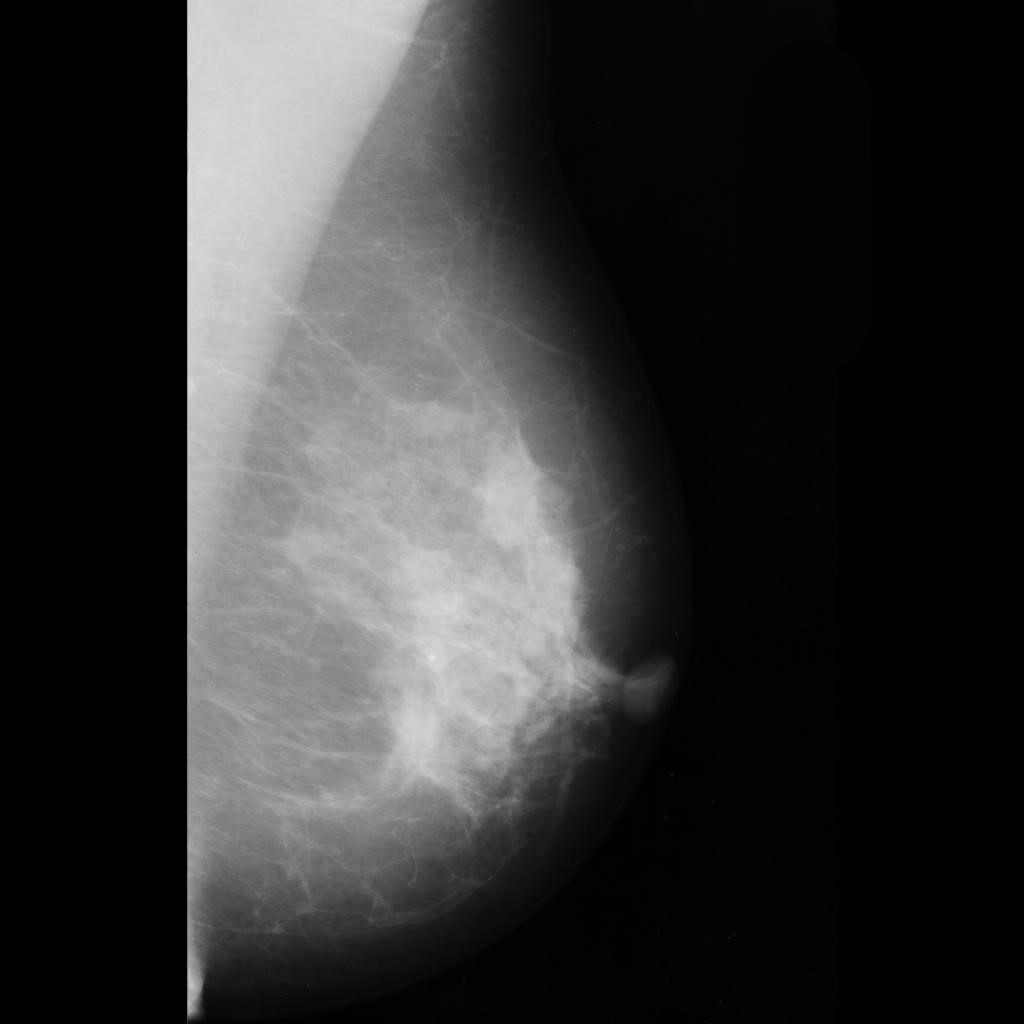

benign